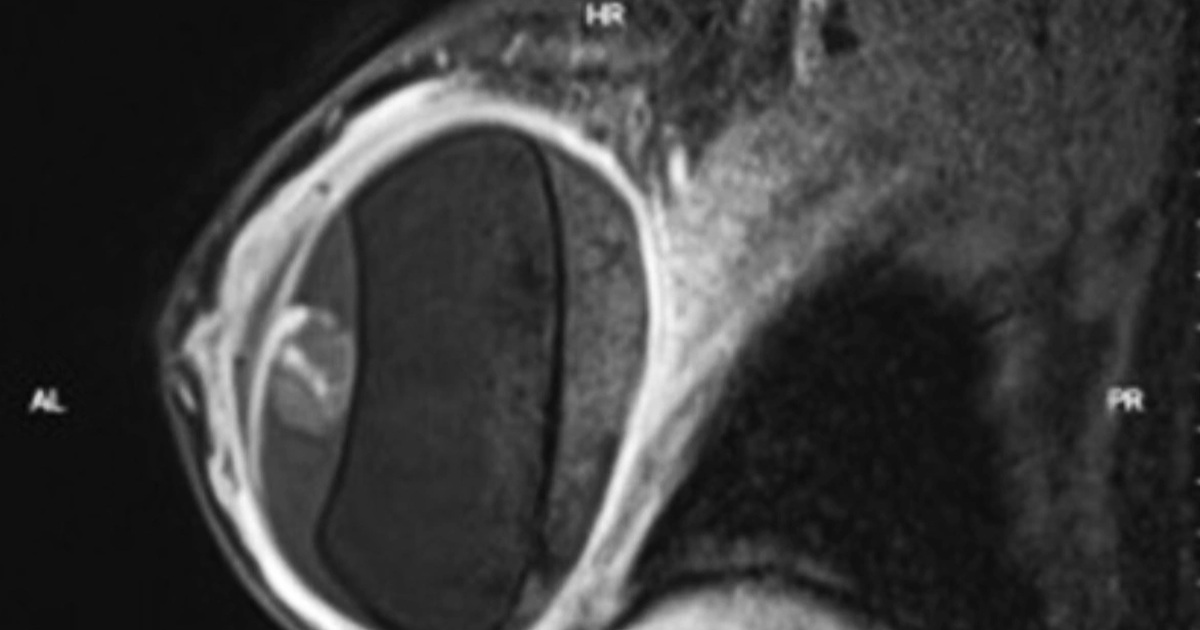

Thời điểm vào Bệnh viện Trưng Vương, bệnh nhân trong tình trạng đau nhiều vùng hạ sườn phải. Qua thăm khám và tiến hành chụp chiếu kiểm tra, các bác sĩ xác định bệnh nhân có sỏi túi mật, cần được phẫu thuật gấp.

Nhờ vậy, cuộc phẫu thuật được thực hiện một cách suôn sẻ, lấy ra đến 481 viên sỏi trong túi mật bệnh nhân. Hậu phẫu, sức khỏe nữ Việt kiều đã dần ổn định.

Số lượng sỏi khổng lồ được lấy ra khỏi túi mật của nữ Việt kiều (Ảnh: BS).